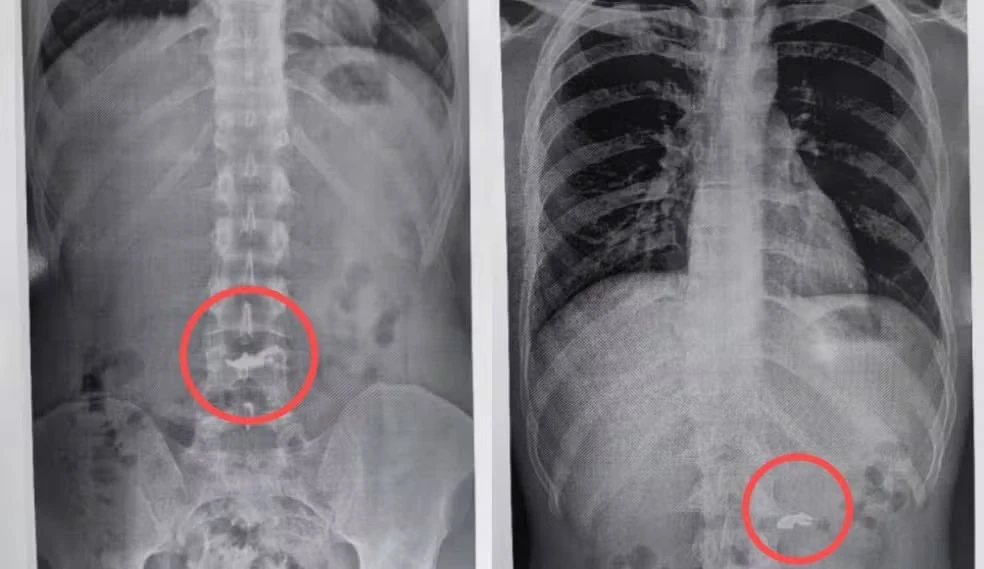

Um caso inusitado chamou a atenção da Polícia Militar de Minas Gerais nesta quarta-feira (30). Um homem de 20 anos foi preso após furtar uma correntinha de ouro e, em uma tentativa desesperada de esconder o crime, engoliu o objeto. A confirmação veio por meio de um exame de raio X.

Os envolvidos foram levados até a UPA São Benedito, também em Santa Luzia, onde foi realizado um exame de raio X. As imagens confirmaram a versão da vítima: a correntinha estava no estômago do suspeito.